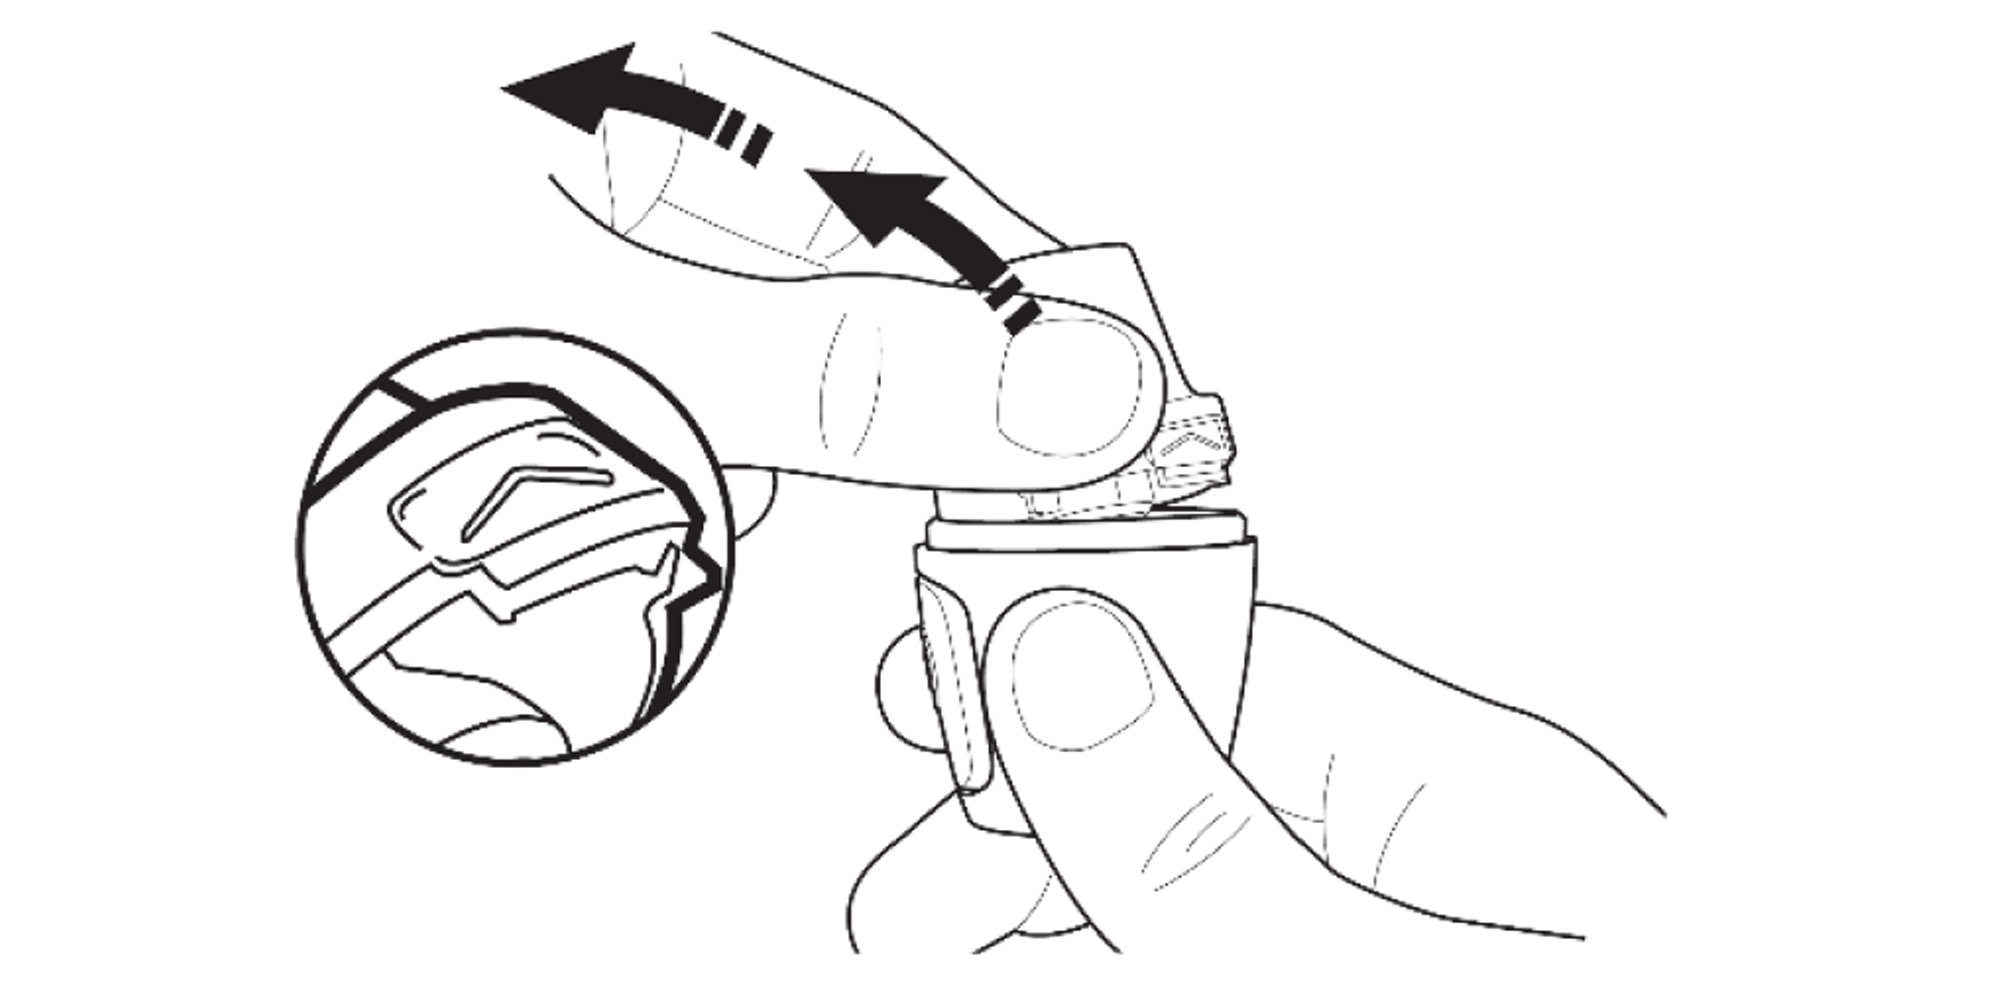

Press the area marked with a chevron. Pull the mouthpiece up and away from the base.